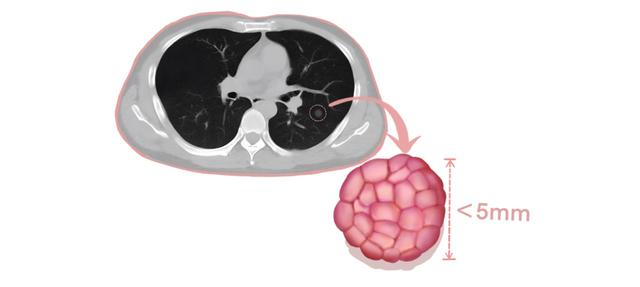

误区:肺磨玻璃结节都是肺癌

错!5mm以下的微小结节,99%为良性结节,每年复查一次即可。